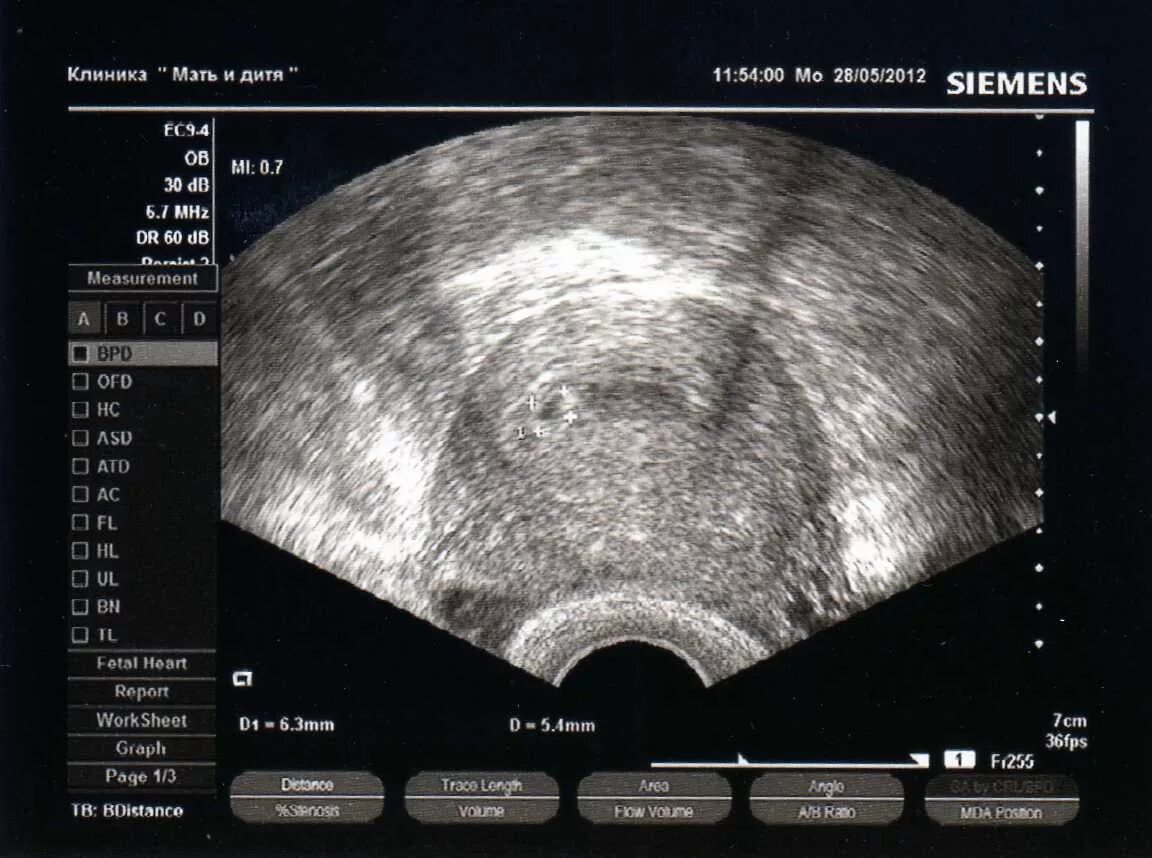

Узи 10 дней беременности